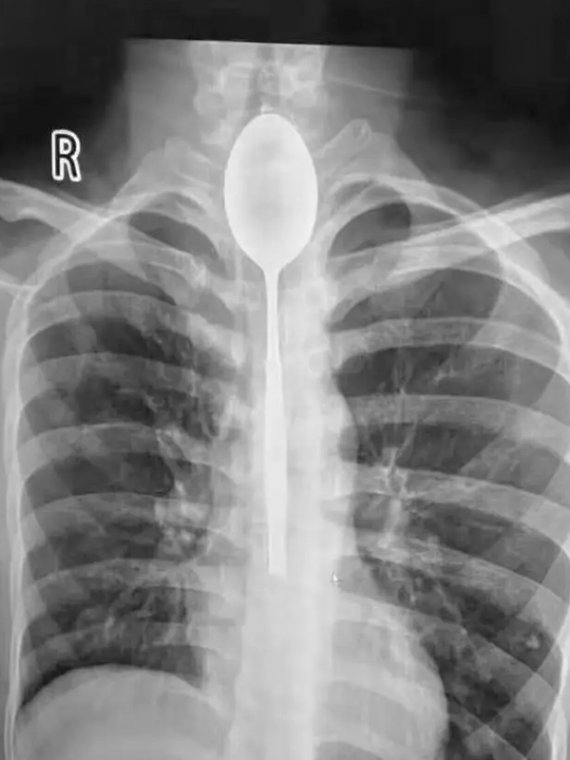

26-річний Чжан звернувся до лікарні в місті Урумчі, Сіньцзян, зі скаргою на гострий біль у грудях. На рентгені…